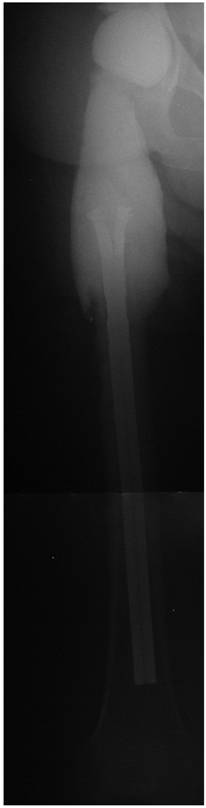

Depending on the particular cause, treatment options may strongly vary. In case of patient incompliance or inability to put partial weight bearing on the operated extremity, the patient should be rather considered as a candidate for a resection arthroplasty and not for a spacer implantation. For prevention of any spacer dislocation due to an insufficient fixation technique onto the proximal femur, a simple “press fit” method should be avoided (Figure 1). Alternatively, a partial (Figure 2) or normal cementation of the spacer into the femoral canal provides the advantage of rotational and axial stability [3]. A normal cementation has the disadvantage in comparison with the partial cementation that all cement debris have to be removed from the femoral canal during the later prosthesis reimplantation, and that during removal of the prosthesis stem osseous defects might occur. Recently, the “glove”-technique has been described as new method for femoral fixation of hip spacers [3]. This method provides a stable fixation onto the proximal femur at facilitating the spacer's explantation since the spacer can be removed at one piece and there is no need for removal of any cement debris compared with other normal cementation techniques.

Figure 1

Articulating hip spacer in situ, the spacer stem is inserted into the femur according to a “press-fit” method.